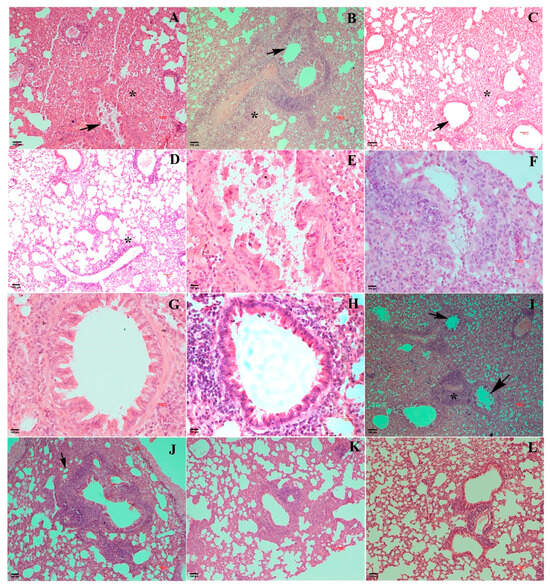

3.4. Pathological Changes Exhibited by EHV1 Mutants Vis-à-Vis Wt Post-Challenge